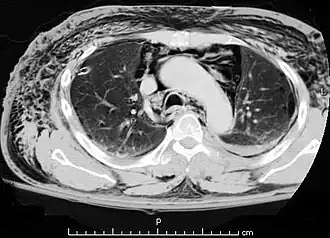

El diagnóstico puede confirmarse mediante una radiografía de tórax en la que aparezca un contorno radiolúcido alrededor del corazón y el mediastino o mediante un TAC de tórax.

Neumomediastino con el signo del ala de ángel.[18] -